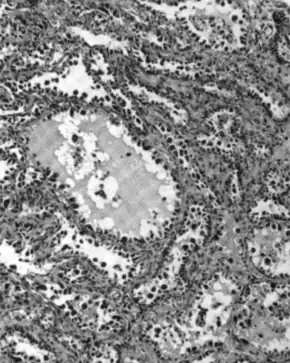

.jpg)

Serous ovarian cancer is the most common type of epithelial ovarian cancer and it accounts for about two-thirds of cases of epithelial ovarian cancer.[28] Low-grade serous carcinoma is less aggressive than high-grade serous carcinomas, though it does not typically respond well to chemotherapy or hormonal treatments.[28] Serous carcinomas are thought to begin in the Fallopian tube.[71][72] High grade serous carcinoma accounts for 75% of all epithelial ovarian cancer.[70] About 15–20% of high grade serous carcinoma have germline BRCA1 and BRCA2 mutations.[70] Histologically, the growth pattern of high grade serous carcinoma is heterogenous and has some papillary or solid growth patterns.[70] The tumor cells are atypical with large, irregular nuclei.[70] It has a high proliferation rate.[70] 50% of the time, serous carcinomas are bilateral, and in 85% of cases, they have spread beyond the ovary at the time of diagnosis.[73]

Serous Tubal Intraepithelial Carcinoma (STIC) is now recognized to be the precursor lesion of most so-called ovarian high-grade serous carcinomas.[73] STIC is characterised by

- Abnormal p53 staining

- Ki67 proliferation index in excess of 10%

- Positive WT1 (to exclude metastases)[73]